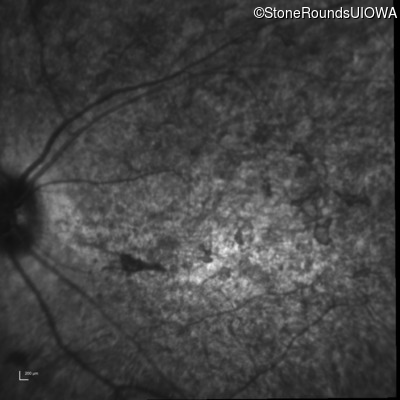

Infrared Fundus Photograph - Right - 20/400 sc

Exemplar